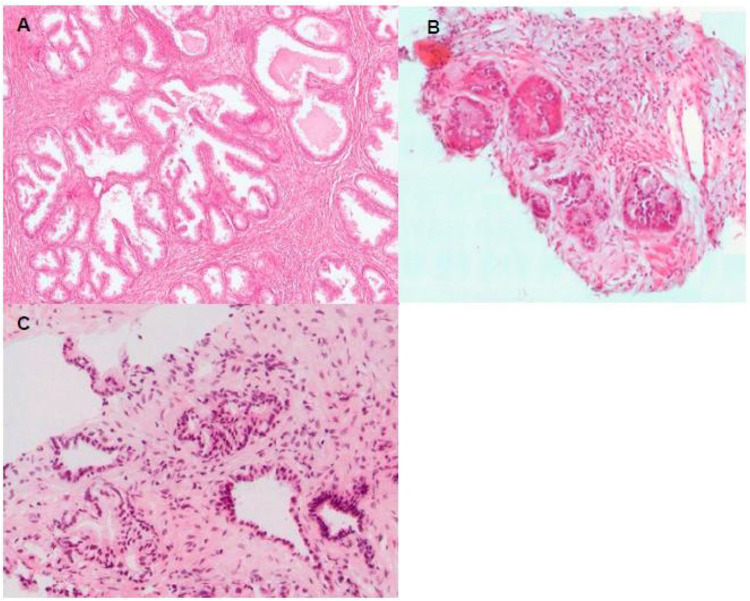

Introduction: Prostate cancer (CaP) is the most common malignancy and the second leading cause of cancer-related deaths among men in Botswana. Currently, diagnosing CaP relies on examining prostate biopsy samples, which can be challenging due to benign mimics. This study aims to evaluate the potential of Alpha-methyl acyl-CoA racemase (AMACR/p504s) and p63, as diagnostic markers for CaP. This may potentially validate the use of immunohistochemistry for detecting CaP in Botswana, where it is not routinely utilized.

Methods: The study included 69 samples, comprising 5 prostatic chip specimens, 50 core biopsies, and 14 radical prostatectomy specimens. These cases were reviewed and categorized into CaP (49 cases) and benign prostatic hyperplasia (BPH) (20 cases). Immunohistochemistry was performed using AMACR/p504s and p63 immunohistochemical stains.

Results: The study found that AMACR/p504s had a sensitivity of 96% and a specificity of 95%, while p63 had a sensitivity and specificity of 100%. PSA levels showed significant positive correlation with AMACR/p504s expression (P < 0.00001).

Discussion: In this study, we have demonstrated the diagnostic utility of AMACR/p504s and p63 due to their high sensitivity and specificity in detecting CaP in Botswana, where these biomarkers are not yet widely used. Furthermore, utilizing these markers in conjunction with other diagnostic tools, such as PSA levels and morphological evaluation, could improve the diagnostic accuracy, especially in challenging cases where histopathological examination alone may be inconclusive.